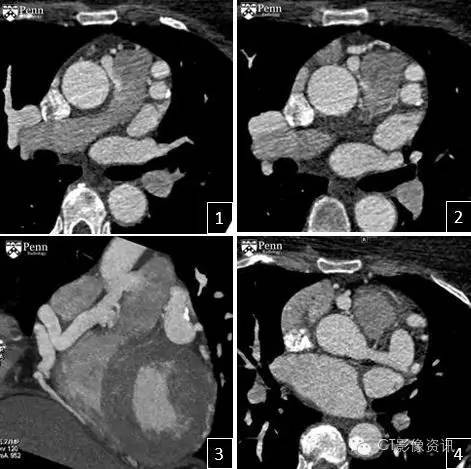

病史 男,46岁,轻微胸痛伴有不典型的心电图改变。心电图表现为:持续性R波低平,ST-T波异常。

冠状动脉CTA图像如下: